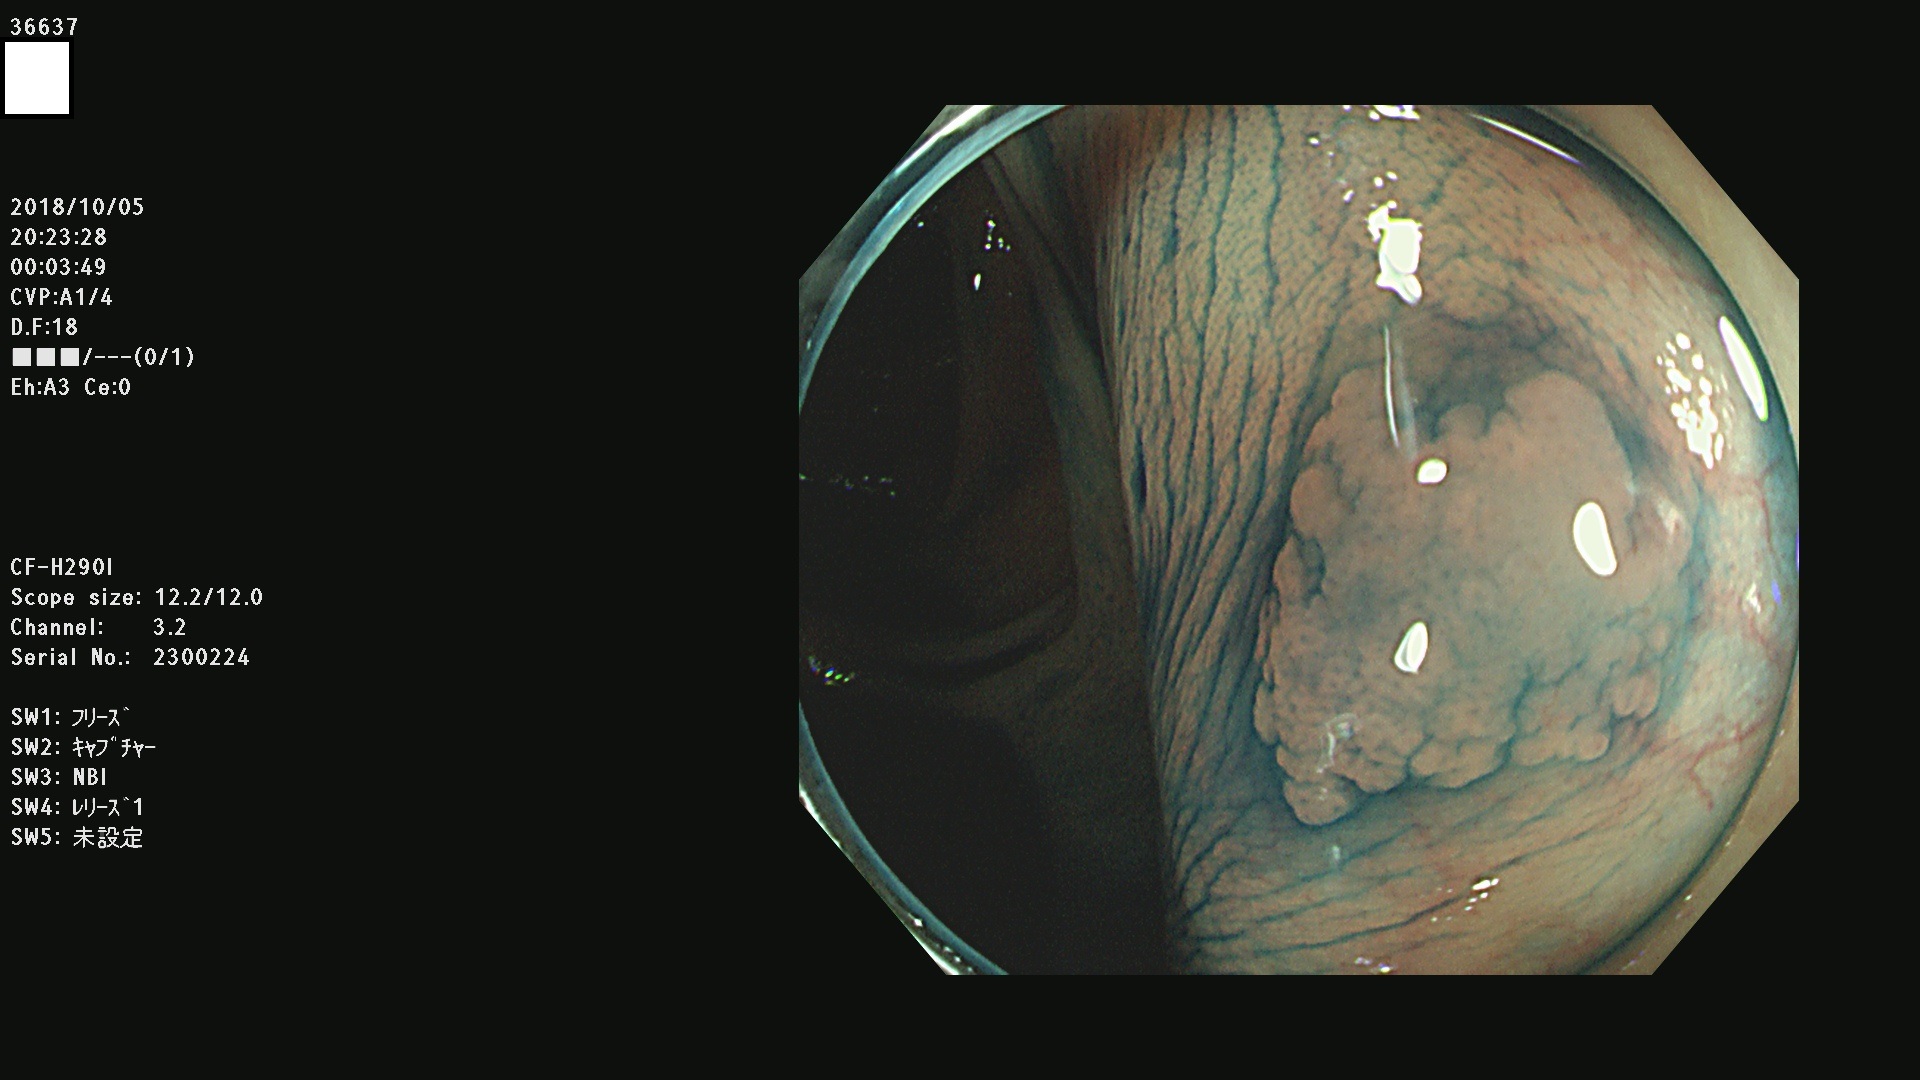

36600 36601 36603 36605 36606 36608 36609 36610 36611 36612 36613 36615 36617 36620 36621 36624 36625 36626 36627 36628 36629 36631(SSAPのみ) 36632 36633 36634 36636(SSAPのみ) 36637(SSAPのみ) 36639 36640 36642 36643 36644 36646 36647 36648 36649(SSAPのみ) 36650(SSAPのみ) 36652 36653 36654 36655(SSAPのみ) 36656 36657 36658 36659 36660 36661(SSAPのみ) 36665 36668 36669 36672 36673 36676 36677 36678 36679 36681 36682 36683 36684 36685 36687(SSAPのみ) 36691 36692 36693 36694 36695 36696 36697 36699(SSAPのみ)

発見困難で危険性の高い平坦型病変(上記100名より抽出)